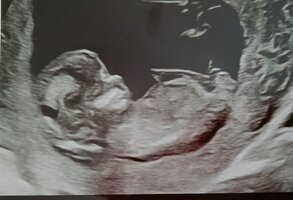

Väsymystä ehkä selkeimpänä ollut, mutta tuntuu että tää alkuraskaus on ollut liiankin helppoa *kopkop*. Välillä ollu jotenki epätodellinenki olo miten ihan tavalliselta onkaan tuntunu, ettei oikein itekään usko että sitä muka on raskaana... Tänään oli nt-ultra ja siellä kaikki hyvin joten päätin että ehkä nyt uskaltaa jo nauttia tästä helposta alkuraskaudesta! Toki vielä seulannan tuloksia pitää odotella.

Hän köllötteli yksiössään oikein tyytyväisenä ja kaikki näytti hyvältä

Todettiin miehen kanssa että toivottavasti hän on syntyessään yhtä helppo kuin mitä on ollut nyt raskausaikana